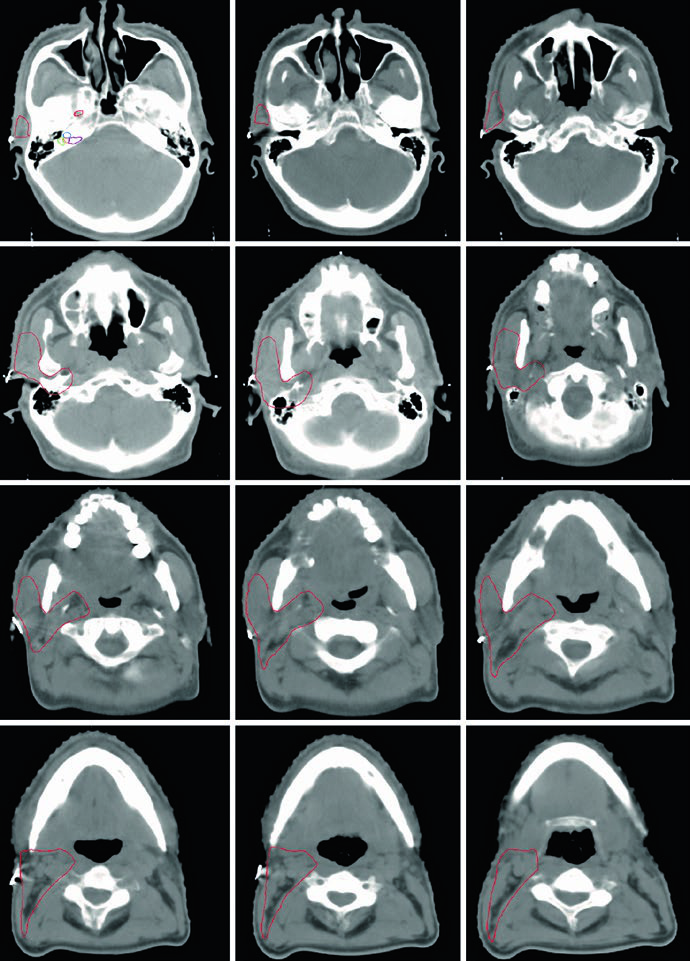

O delineamento das estruturas da base do crânio deve ser realizado com janela óssea na TC. As principais referências incluem: o forame oval (vermelho), a cóclea (azul), o vestíbulo (laranja), o canal auditivo interno (violeta) e os canais semicirculares (verde). Identificar corretamente essas estruturas é fundamental para garantir cobertura adequada do trajeto neural sem irradiar excessivamente estruturas sensíveis como a cóclea.

As imagens da TC demonstram o trajeto do nervo glossofaríngeo em diferentes cortes axiais. O nervo pode ser identificado posterolateral ao processo estiloide, descendo junto à carótida interna. A marcação oval vermelha nos cortes mostra a localização esperada do nervo ao longo de seu percurso cervical. O último corte utiliza janela de partes moles para melhor visualização das relações entre o nervo e os vasos cervicais.